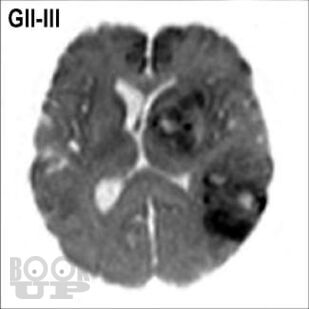

Книга «Опухоли мозга. КТ- и МРТ-диагностика» посвящена диагностике опухолевого поражения центральной нервной системы. При этом широко раскрыты особенности морфологической структуры каждой конкретной опухоли головного мозга. Структура изложения материала основана на классификации опухолей головного мозга по рекомендациям ВОЗ. Представленные опухоли в заголовке содержат шифр МКБ/О из 10-го пересмотра. Под каждым диагностическим изображением имеется подпись с обозначением его характеристик: метод исследования (КТ, МРТ, рентген, ПЭТ и др.), название ширины окна для КТ или импульсной последовательности на МРТ, а также ориентация среза в пространстве (аксиальный, сагиттальный или корональный). Данная особенность позволяет улучшить восприятие изображений, а также избежать путаницы при сопоставлении разных импульсных последовательностей и окон на МРТ и КТ.